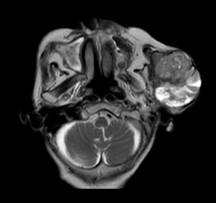

Hình ảnh khối u trên phim cộng hưởng từ